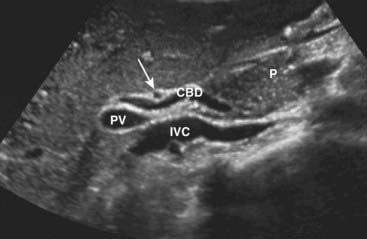

image Ultrasound plays a key role in evaluation of the intrahepatic and extrahepatic bile ducts and pancreatic duct. The intrahepatic biliary radicals drain into the left and right hepatic ducts, which join to form the common hepatic duct (CHD). Where the cystic duct from the gallbladder joins the CHD is the origin of the common bile duct (CBD), which drains either within or adjacent to the head of the pancreas via the ampulla of Vater into the second portion of the duodenum. The CBD lies anterior to the portal vein and lateral to the hepatic artery in the porta hepatis (Fig. 19-7).

Figure 19-7 Normal common bile duct, portal vein, and hepatic artery, sagittal view.

The common bile duct (CBD) measures 3 mm (normal <6 mm). The solid white arrow points to the hepatic artery, seen on end. The portal vein (PV) is posterior to the common duct, and the inferior vena cava (IVC) is seen posterior to the portal vein. The pancreas (P) is anterior to the CBD.

imageThe CHD and proximal CBD can be visualized normally on virtually all ultrasound studies of the right upper quadrant. The CHD measures no more than 4 mm (inner wall to inner wall) and the CBD measures no more than 6 mm in diameter. The pancreatic duct measures <2 mm.